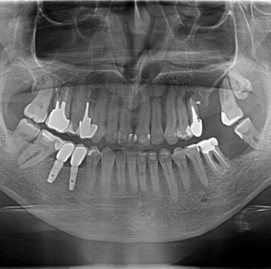

Lat 50, pół roku przed rozpoczęciem leczenia implantologicznego przestał palić papierosy. Znacząca poprawa higieny, pacjent silnie zmotywowany. Po regeneracji kości i rekonstrukcji tkanek miękkich odbudowa sześciu zębów na koronach porcelanowych. Na zdjęciu widoczna ilość i jakość tkanki kostnej po rekonstrukcji. W porównaniu ze stanem początkowym uzyskano znaczącą poprawę warunków kostnych nie do osiągnięcia metodami sterowanej regeneracji kości z użyciem reklamowanych markowych błon kolagenowych i dosypaniem kości z butelki.

Implantacja natychmiastowa. Zęby paradontyczne. Usuniete zgodnie z popularną obecnie na zachodzie techniką: usuń zęby zanim zaniknie kość. Wynikiem takiego postępowania jest mniejsza trauma dla pacjenta i krótszy okres trwania rehabilitacji protetycznej, niższe całkowite koszty leczenia. Ale jednocześnie więcej implantów i mniej własnych zębów. W długotrwałym okresie obserwacji takie podejście daje dobre wyniki.

Pacjent z długą historią leczenia implantologicznego. Pierwsze implanty w pozycjach 23, 24 miał wkręcane w Warszawie przed 25 laty. Implant w pozycji górnego prawego kła ma agresywny gwint, ponieważ bezpośrednio po implantacji był obciążony (immediate loading) tymczasowym atachmentem ball abutmentv do stabilizacji tymczasowej protezy ruchomej. Kość szczęki regenerowana i odbudowywana etapami w całym górnym prawym kwadrancie. Pacjent planuje uzupełnić brakujące zęby 25, 26.

Lat 38, Pacjent paradontyczny, obciążony genetycznie, niepalący, dobra higiena. Pionowa i pozioma regeneracja kości.

Pacjentka lat 72, od kilkudziesięciu lat chorująca na cukrzyce I typu, obecnie od 10 lat na pompie insulinowej. Profesor medycyny, siostrzenica pacjentki prowadzi swoją ciocię diabetologicznie, pacjentka świadoma zagrożeń przy zabiegach regeneracji kości i implantacji w takim ogólnym stanie zdrowia. Po rekonstrukcji tkanek miękkich i kości osadzono dwa implanty o średnicy 5,0 mm. Na zdjęciu śródzabiegowym widać zadowalające wyniki rekonstrukcji tkanki kostnej. Po upływie kilku miesięcy wykonano nadbudowę protetyczną.

Pacjentka po ekstrakcji kilku zębów, z implantacją natychmiastową, odroczoną. Zdjęcie pantomograficzne wykonano pięć lat po implantacji. Widoczna stabilna sytuacja kostna i dziąsłowa.